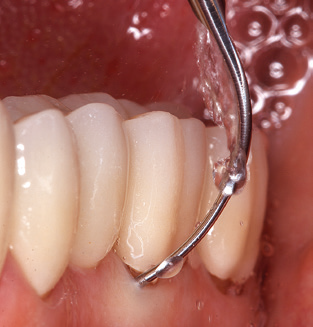

Das aktuelle Arbeitskonzept für die UPT

Die Aktualisierung der Anamnese stellt im Rahmen der UPT eine zentrale Maßnahme dar, sie sollte mindestens einmal jährlich erfolgen. Sie dient dazu, mögliche neue Risikofaktoren zu erkennen und zu dokumentieren. Vor allem dann, wenn ein Patient langjährig betreut wird, ist es wichtig, zu erfahren, ob sich patientenspezifische und allgemeinmedizinische Risikofaktoren verändert haben. Hier sollte an erster Stelle an ein erhöhtes Risiko durch Diabetes gedacht werden, aber auch andere allgemeinmedizinische Erkrankungen (kardiovaskuläre Erkrankungen und Neoplasien) können aufgrund der erfolgten Therapien und der notwendigen Medikamenteneinnahme zu einem veränderten Risikoprofil führen. Das Update der Anamnese ist also auch im Rahmen der UPT sehr wichtig, um gegebenenfalls aufgrund eines veränderten Risikoprofils eine Veränderung des Behandlungsintervalls zu veranlassen. Im nächsten Schritt ist es wichtig, der Diagnostik besondere Aufmerksamkeit zu schenken. Die Instrumentation ist zwar ein zentraler Bestandteil der UPT, in keinem Fall sollte sie aber Bestandsaufnahme und Dokumentation verdrängen. Für die Diagnose ist dabei der parodontale Befund unerlässlich, eine Zunahme der Sondierungstiefen und eine Erhöhung des BOP­Index sind zentrale Indikatoren für eine Progression parodontaler und periimplantärer Erkrankungen. Zum Erheben der benötigten Daten darf daher nicht davor zurückgeschreckt werden, auch Implantate zu sondieren. Dabei ist es wichtig, dass hierfür millimeterskalierte PAR­Sonden verwendet werden. Für die Sondierungsbefunde an natürlichen Zähnen haben sich seit Jahrzehnten metallische Sonden bewährt. Bei Implantaten ist die Herausforderung für das Erheben korrekter und reproduzierbarer Sondierungsbefunde größer. Da es durch die Diskrepanz von Implantatdurchmesser und Kontur der Suprakonstruktion regelmäßig zu einer Überkonturierung der Suprastruktur kommt, sind für Sondierungen an Implantaten flexible, aber dennoch millimeterskalierte Son­ den sehr sinnvoll (z. B. Colorvue Kit PCV11KIT6, Hu­Friedy; Abb. 4).

Abb. 4: Für das Sondieren an dentalen Implantaten sind biegsame, millimeterskalierte Sonden empfehlenswert (z.B. Colorvue Kit PCV11KIT6, Hu-Friedy). – Abb. 5a und b: Eine gerade Arbeitsspitze (1P, W&H Dentalwerk Bürmoos GmbH) ist universell für die Instrumentierung natürlicher Zähne geeignet. – Abb. 6: Für die Bearbeitung schwer zugänglicher Bereiche der Zahn- und Wurzeloberflächen (z.B. Furkationen) bieten sich gebogene Arbeitsspitzen (3Pr/3Pl, W&H Dentalwerk Bürmoos GmbH) an. – Abb. 7: Die spitz zulaufende sechseckige Implantatreinigungsspitze (1I, W&H Dentalwerk Bürmoos GmbH) ermöglicht eine atraumatische und effiziente Reinigung der Kronen- und Abutmentoberflächen. – Abb. 8: Für die manuelle Instrumentierung der Implantatoberflächen sind Titan- oder Carbonküretten geeignet.